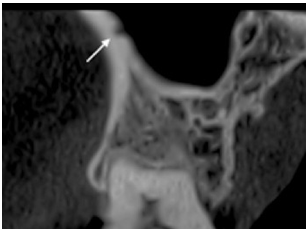

El suministro de sangre al seno maxilar, está proporcionado por 4 ramas principales: la arteria alveolar superior posterior, la arteria infraorbitaria, la arteria palatina descendente y la arteria esfenopalatina. El abordaje de la técnica de ventana lateral, es la que presenta mayor riesgo en dañar los vasos sanguíneos en esa área, especialmente la arteria ASP. (Fig. 1) La posibilidad y el grado de severidad de la hemorragia dependen del diámetro de la arteria (29,30,31). Por lo tanto, es de suma importancia realizar un adecuado estudio pre quirúrgico del área, usando técnicas avanzadas, como el uso de la tomografía computarizada (CBCT). (Fig. 2) El uso de las CBCTs, ha demostrado ser una herramienta indispensable para el diagnóstico e identificación de estructuras anatómicas para una correcta elección de abordaje quirúrgico, en especial cuando la arteria ASP es mayor a 0.5 mm (32,33). Varios factores y variables de pacientes, como edad, género, estado de dentición, volumen de seno, altura y ancho pueden influenciar en la localización de la arteria.